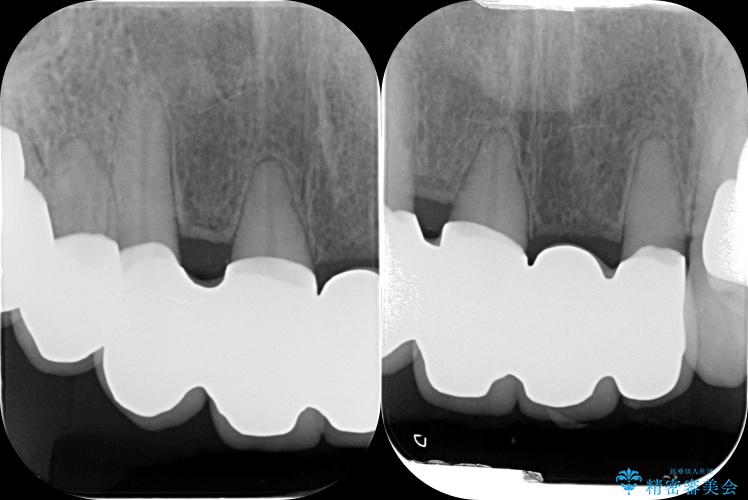

まず、保存の難しい歯を抜去したのち矯正治療を行い歯並びの改善、歯周ポケットを除去したことで安定した歯周環境、咬合関係を作り出すことができました。

治療中

歯の総合的なマネージメントを行う包括的歯科治療の実践[ 歯周病・矯正・セラミック補綴 ] 治療中画像 歯の総合的なマネージメントを行う包括的歯科治療の実践[ 歯周病・矯正・セラミック補綴 ] 治療中画像 歯の総合的なマネージメントを行う包括的歯科治療の実践[ 歯周病・矯正・セラミック補綴 ] 治療中画像 歯の総合的なマネージメントを行う包括的歯科治療の実践[ 歯周病・矯正・セラミック補綴 ] 治療中画像 歯の総合的なマネージメントを行う包括的歯科治療の実践[ 歯周病・矯正・セラミック補綴 ] 治療中画像 歯の総合的なマネージメントを行う包括的歯科治療の実践[ 歯周病・矯正・セラミック補綴 ] 治療中画像 歯の総合的なマネージメントを行う包括的歯科治療の実践[ 歯周病・矯正・セラミック補綴 ] 治療中画像 歯の総合的なマネージメントを行う包括的歯科治療の実践[ 歯周病・矯正・セラミック補綴 ] 治療中画像 歯の総合的なマネージメントを行う包括的歯科治療の実践[ 歯周病・矯正・セラミック補綴 ] 治療中画像 歯の総合的なマネージメントを行う包括的歯科治療の実践[ 歯周病・矯正・セラミック補綴 ] 治療中画像 歯の総合的なマネージメントを行う包括的歯科治療の実践[ 歯周病・矯正・セラミック補綴 ] 治療中画像